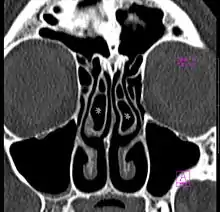

Concha bullosa

A concha bullosa is a pneumatized (air-filled) cavity within a nasal concha, also known as a turbinate.[1] Bullosa refers to the air-filled cavity within the turbinate.[1] It is a normal anatomic variant seen in up to half the population. Occasionally, a large concha bullosa may cause it to bulge sufficiently to obstruct the opening of an adjacent sinus, possibly leading to recurrent sinusitis[1] and various head pains related to areas innervated by the trigeminal nerve.[2] In such a case the turbinate can be reduced in size by endoscopic nasal surgery (turbinectomy). The presence of a concha bullosa is often associated with deviation of the nasal septum toward the opposite side of the nasal cavity.[3]